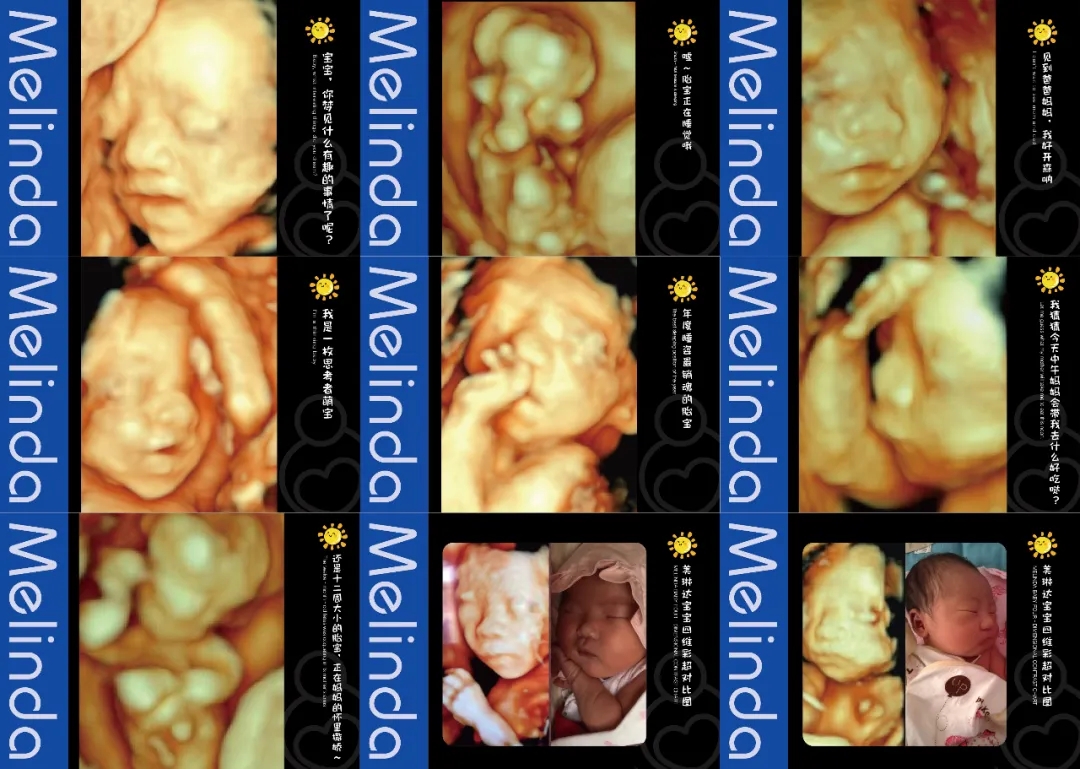

大屏幕同时播放宫内情况(躺床上可以清晰的看到胎宝情况)检查床旁放置舒适纯皮沙发,支持家属陪伴检查。重要的是,美琳达也会提供胎儿写真照片,留作纪念。

(美琳达四维宝宝照片)